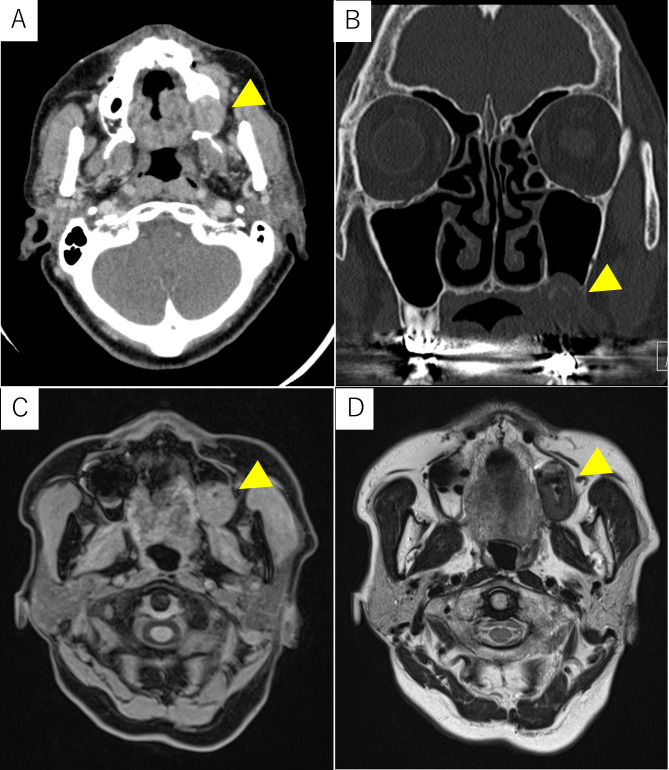

Case presentation: An 81-year-old woman was referred to our department because of swelling of the left maxillary gingiva. The left maxillary second molar had been extracted more than 10 years earlier. Surgical biopsy was performed, and histopathological findings indicated a foreign body granuloma. The patient underwent tumorectomy, during which we found a yellowish tumor. The pathologic findings were the characteristic crystal deposition, fibril-like crystals, and giant cells around the crystals. Gold hydroxamic acid staining revealed positivity for the crystals. The final pathological diagnosis was PCDD. The patient had no further symptoms and no disease recurrence.

Conclusions: It is relatively easy to diagnose PCDD from the characteristic histopathological findings; however, it may be overlooked by pathologists who are unaware of the disease. T2-weighted magnetic resonance imaging of PCDD in the jawbone has depicted low intensity, a finding that differs from those of ordinary cancers and odontogenic tumors. The oral cavity often undergoes surgical procedures, and PCDD may form, and grow.